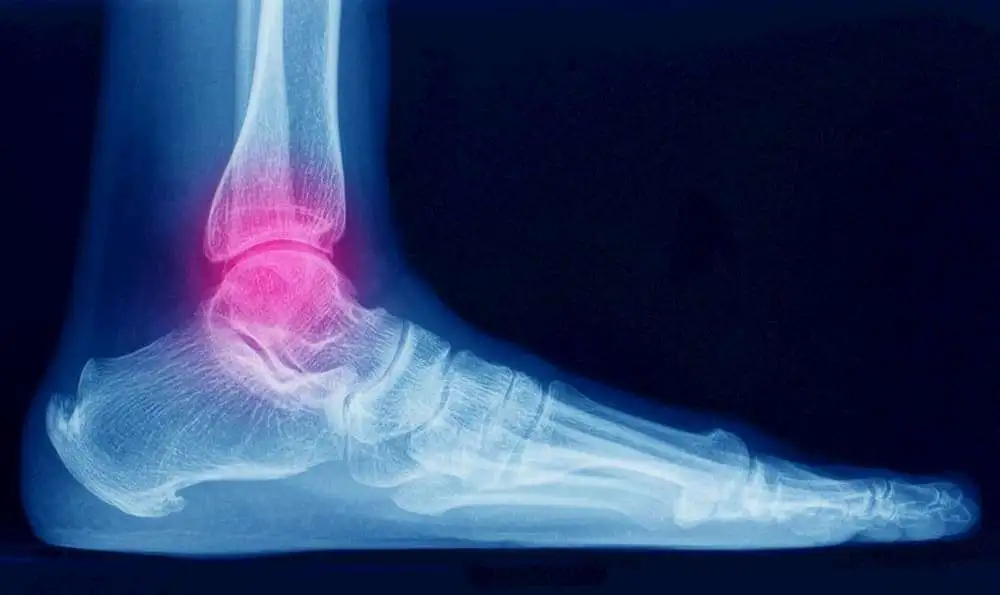

Chronic ankle instability is a state indicated by a recurring “giving way” of the outer (lateral) side of the ankle. In this study, the efficacy of the rehabilitation techniques has been revealed sensibly for chronic ankle instability management.

There is minimal patient-oriented evidence regarding the effectiveness of interventions targeted to reduce symptoms associated with chronic ankle instability (CAI). Additionally, clinicians aiming to prioritize care by implementing only the most effective components of a rehabilitative program have very little evidence on comparative efficacy. To assess the comparative efficacy of two common ankle rehabilitation techniques [wobble board (WB) balance training and ankle strengthening using resistance tubing (RT)] using patient-oriented outcomes.